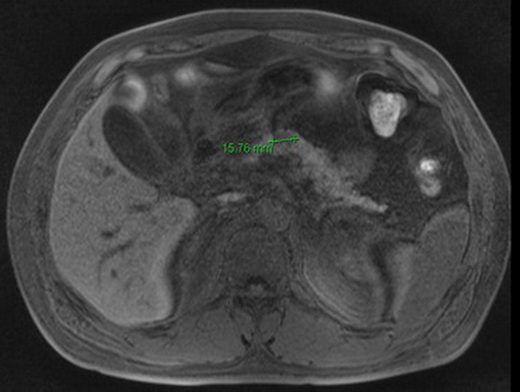

MRT Pankreas+MRCP nativ+KM: Das Pankreas zeigt li. paramedian im Corpus eine lediglich nativ zu erkennende, maximal 16 mm messende Läsion, die in der arteriellen und venösen Perfusionsphase in etwa sich der Signalintensität des Pankreas angleicht. Lokoregionär keine pathologisch vergrößerten Lymphknoten, der Pankreasgang unauffällig. MR-tomographisch Nachweis einer gut vaskularisierten, und gut 16 mm großen Läsion an der Vorderfläche des Pankreaskorpus li. paramedian, die gut vereinbar ist mit dem klinischen Bild eines Insulinom.

Abb. 180:

Abb. 181:

Abb. 182: